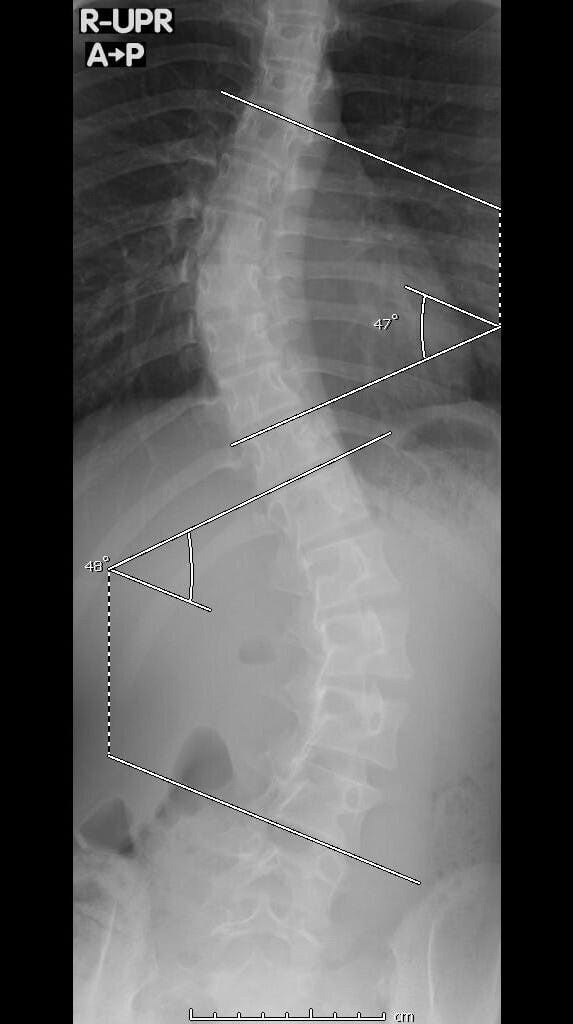

私はカンボジアに住んでいた時に偶然家族によって重度特発性側弯症が発見されました。ですが、矯正器具と理学療法のおかげで今後手術が不要なレベルまで改善しました。私も実際に側弯症と診断されてから知ったのですが、思春期特発性側弯症という病気は思春期の子供たちの100人に2、3人発症するそうです。そして、特発性側弯症の発症原因はいまだ不明です。悪化するとひどい腰背部痛や、重度の場合には内臓の圧迫によって呼吸困難や心不全にも陥り、発見が遅いと侵襲性の高い手術をするしかありません。日本には学校検診の中に、側弯症検診というものがありますが、私の住んでいたカンボジアでは学校検診さえもなく、私の側弯症の発見も遅れてしまいました。